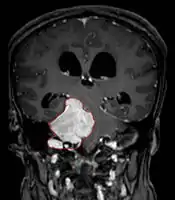

Imaging

- Benign Meningioma on MRI

- MRI

- Preferred imaging because it can show dural origin

- Dural tail sign seen in about two-thirds: characteristic marginal thickening that tapers peripherally along the dura

- Isointense on T1, hyperintense (usually homogeneously) on T2, strong enhancement with IV contrast